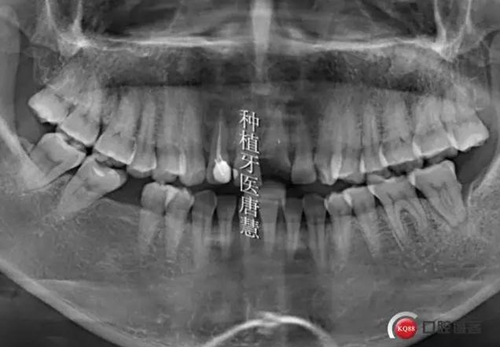

植入植體

5.jpg

植體位于腭側(cè)骨緣下1mm

6.jpg